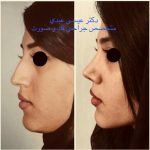

دکتر عیسی عبدی در رشت

دکتر عیسی عبدی در رشت

– متخصص جراحی فک , پلاستیک صورت و بینی

جراحی فک , پلاستیک , صورت وبینی

جراحی ترمیمی و زیبایی فک و صورت و جمجمه و گردن